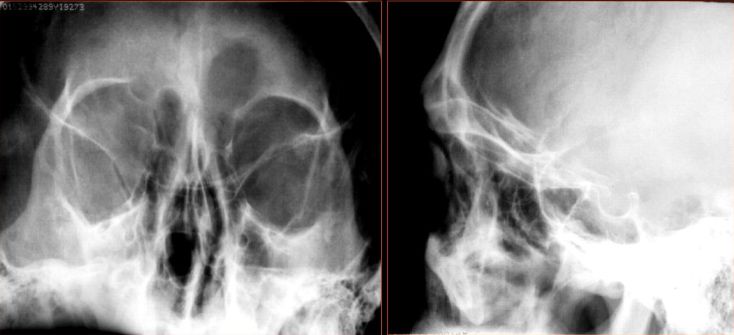

平片及CT检查表现

Water氏位:窦腔混浊,液平面

急性鼻窦炎